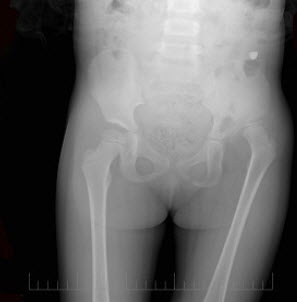

75、单项选择题

女,根据其正常骨盆影像图像,判断其最可能的年龄()